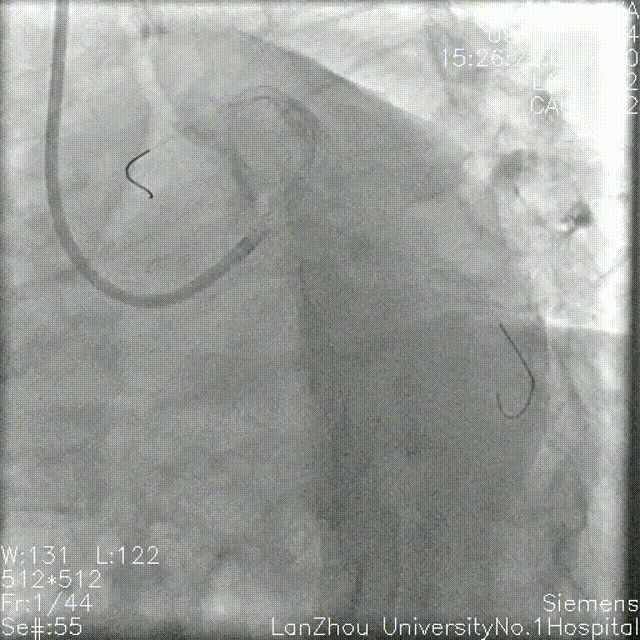

头位造影:

LM较短,末端可见重度狭窄,前降支近中段全程弥漫性狭窄伴钙化;

回旋支次全闭,可见钙化影。

右肩造影:

前降支近中段全程弥漫性狭窄伴环形钙化,最重处95%狭窄;

对角支开口狭窄不重,角度不大,可能不需要导丝保护。

蜘蛛位造影:

左主干开口、体部未见明显狭窄;

第一对角支开口重度狭窄;

回旋支次全闭,开口、近端、中段重度狭窄,可见环形钙化。

右冠造影:

全程斑块伴有钙化;

第二弯可见支架影,支架未见明显再狭窄。